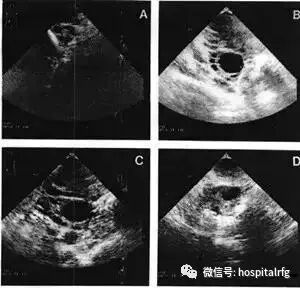

B超监测排卵

在应用促排卵药后或自然周期中,最好采取B超检测排卵。即在月经周期第8—10天开始,观察优势卵泡的出现和发育,一直到排卵。如果卵泡直径小于17毫米,则妊娠的可能性很小。同时超声监测还可以清晰观察子宫内膜的厚度和形态,对预测妊娠有一定的作用。